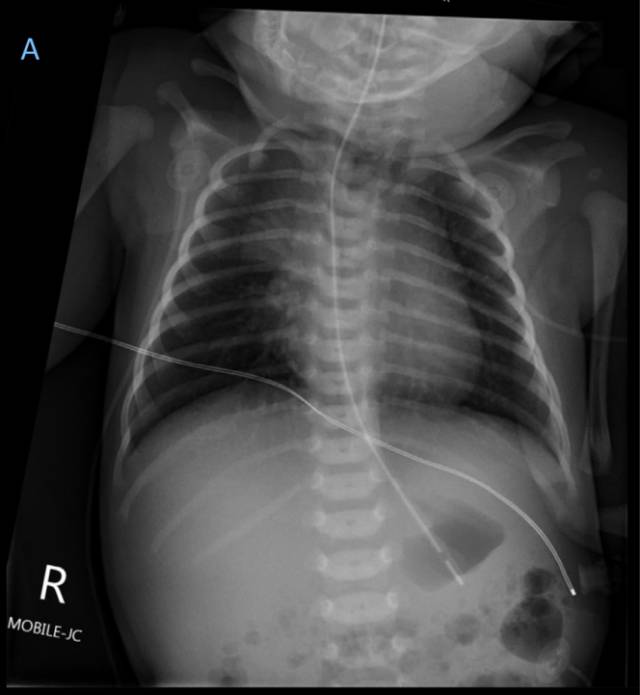

An 89-year-old woman was treated in our intensive care unit with Escherichia coli urosepsis. The patient developed multiple organ failure and became intubated and mechanically ventilated. On the third intensive care day, a new 16Fr. type “Levin” nasogastric tube was inserted for enteral feeding. As no anatomical abnormalities were described, we followed a blind insertion technique, encountering no resistance while advancing the tube towards the stomach, and final position was confirmed by auscultation of a gurgling noise over the epigastrium. Enteral nutrition was started, according to ICU feeding protocol. However, 48 h later, acute hemodynamic instability was observed and invasive mechanical ventilation became difficult. A bed-side ultrasonography showed a pleural effusion on the right side, and a puncture for pleural-catheter placement revealed nutrition in the pleural space. 3D-reconstructed images of a chest computed tomography (Fig. 1a, arrow) demonstrated the endpoint of the nasogastric tube into the right pleura, confirming the perforation of the right lower lobe bronchus and massive lung parenchyma damage (Fig. 1b), despite the patient having an endotracheal tube in situ and giving no signal of cuff insufficiency. We suggest that radiological control remains the standard procedure to confirm the correct position of a nasogastric tube, even by invasive ventilated patients.

一名89岁女性患者因大肠杆菌泌尿系感染导致sepsis在ICU接受治疗。患者出现多器官功能衰竭,接受气管插管和机械通气。入住ICU的第三天,置入16 F的Levin型鼻胃管进行肠内营养。由于未发现任何解剖学异常,我们采用盲法置入,将鼻胃管送入胃内时未遇到任何阻力,置管结束后在上腹部听诊到气过水声确认导管位置。根据ICU喂养方案开始肠内营养。然而,48小时后,患者出现血流动力学不稳定,有创机械通气难以维持。床旁超声检查显示右侧胸腔积液,置入胸腔引流管发现胸腔积液为营养液。胸部CT检查三维重建(图1a,箭头)显示鼻胃管末端位于右侧胸腔内,确诊右下叶支气管穿孔及大面积肺实质损害(图1b)(尽管患者有气管插管且没有套囊漏气的表现)。我们建议,即使对于接受有创机械通气的患者,影像学检查仍然是确认鼻胃管位置正确与否的标准措施。